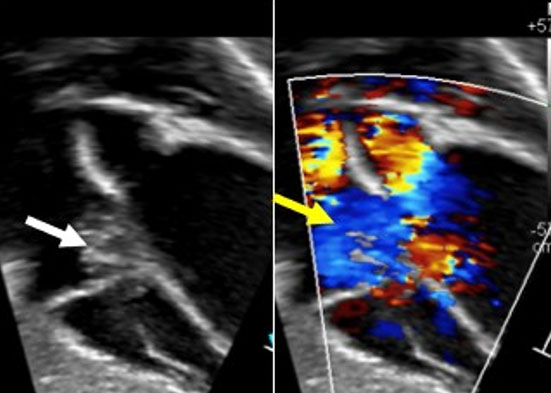

A transthoracic echocardiogram performed showed a large mobile heterogenous echogenic mass attached to the anterior leaflet of the tricuspid valve, without obstruction to inflow. During systole, the mass prolapsed through the valve causing leaflet distortion and mild-to-moderate eccentric tricuspid regurgitation (Figure 1). The heart structure and function were otherwise normal. Cardiac magnetic resonance imaging (CMR) was performed for diagnostic tissue characterization. On steady state free precession (SSFP) sequences, the mass appeared as isointense, well circumscribed, mobile valve nodules with turbulent flow. Tissue characterization revealed a T1 hypointense and T2 isointense soft tissue mass without early perfusion or late gadolinium enhancement (Figure 2). Imaging findings were consistent with a benign tumor with the differential diagnosis of an infectious or inflammatory mass, myxoma, papillary fibroelastoma, or teratoma [1].

Figure 1: Subcostal color compares transthoracic echocardiogram imaging showing a nodular appearing mass (white arrow) attached to the tricuspid valve leaflet. The mass prolapses in systole into the right atrium resulting and results in moderate tricuspid regurgitation (yellow arrow).